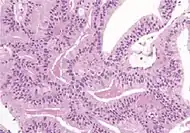

Intraductal carcinoma of the prostate with an infiltrative growth pattern may be morphologically difficult to distinguish from invasive cancer. One focus shows comedonecrosis (arrow), morphologically suggesting Gleason pattern 5 invasive carcinoma (a haematoxylin and eosin, b CK5/6)[19]

Intraductal carcinoma of the prostate with very patchy basal cells identified by immunohistochemistry. At least some of the glands lacking basal cell immunoreactivity represent intraductal rather than invasive carcinoma (a haematoxylin and eosin, b CK 5/6)[19]